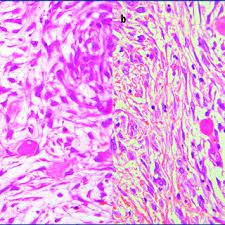

Veterinary Sciences Free Full Text Pathological Findings Of Canine Idiopathic Pericarditis And Pericardial Mesotheliomas Correlation With Clinical And Survival Data Html

Asbestos fibers trapped inside the body lodge in the lining of the chest, abdomen, or heart resulting in inflammation, irritation, and scarring. Malignant mesothelioma is an uncommon tumor arising mostly from the serosal surface of the pleural or peritoneal cavity .in most human patients, pleural mesothelioma is a locally advanced tumor and the invasion of the thoracic wall with rib involvement has been reported 2, 3.a locally invasive nature of malignant mesotheliomas has rarely been reported in dogs, while involvement of ribs has. Asbestos can also be a cause of a specific form of lung cancer, called mesothelioma, just as it is in humans. One study revealed more asbestos bodies were found in dogs with mesothelioma than in control dogs. mesothelioma is a rare and aggressive tumor that, in many cases, results from exposure to asbestos. With the recognition and establishment of the root cause of mesothelioma, law services have equipped themselves to counter effect its fallout. 00:00:30 because cardiac disease is extremely common, and mesothelioma is extremely rare, well, that leads to difficulty fighting these mesothelioma, cause you don't look for it. This cancer is caused by asbestos exposure, which may have occurred in someone's home, workplace, or community. Mentioned a mesothelioma in a dog, with pericardial location. In contrast, the attributable risk for lung cancer (90 percent) associated. With so many factors already consuming a patient's time and energy, financial burdens only add on to the stress of a poor diagnosis. Peritoneal mesothelioma patients face an average life expectancy of six to 12 months. Recommending a product that is easy for the client to administer correctly can significantly improve the.